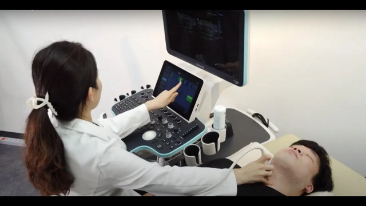

Resona 7

Ultrason Yenili?i Konusunda Yeni Dalgalar

Mindray, ?irketin kuruldu?u gĂŒnden bu yana sĂŒrekli olarak tan?sal do?rulu?u iyile?tirmeye ?al??maktad?r. Devrim niteli?indeki ZONE Sonography? Teknolojisi ile desteklenen Resona 7ânin yeni ZST+ platformu, b?lge g?rĂŒntĂŒsĂŒ alma ve kanal veri i?leme ?zellikleri ile ultrason g?rĂŒntĂŒsĂŒ kalitesini daha ĂŒst bir dĂŒzeye ??kar?yor.

Resona 7, ĂŒstĂŒn dĂŒzeyde g?rĂŒntĂŒ kalitesine ek olarak, vaskĂŒler hemodinamik de?erlendirmesi i?in devrim niteli?indeki V Ak??? ile fetĂŒs CNS tan?lamas? i?in 3 boyutlu veri kĂŒmesinden dĂŒzlem g?rĂŒntĂŒsĂŒ alma konusunda en iyi birime sahip oldu?undan, klinik ara?t?rma yeterliklerini de art?rmaktad?r. En sezgisel, harekete dayal? ?oklu dokunmatik i?letim ile tĂŒm temel klinik ?zellikleri bir araya getiren Resona 7, ultrason yenili?i konusunda ger?ek anlamda yeni dalgalara ?ncĂŒlĂŒk ediyor.